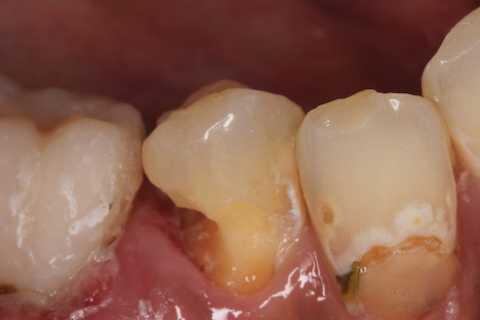

残根上のCR8 2025.10.28